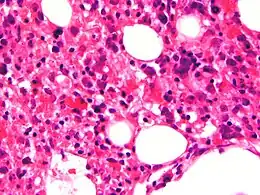

Moelle osseuse avec prolifération de macrophages contenant des globules rouges dans leurs cytoplasmes.

• Hémophagocytose dans la moelle osseuse ou dans la rate voire dans les ganglions lymphatiques. Ces cellules sont des macrophages avec présence d'éléments hématopoïétique dans le cytoplasme. Elles sont inconstamment retrouvées[7] et peuvent être également présentes en dehors de la lymphohistiocytose hémophagocytaire[8].